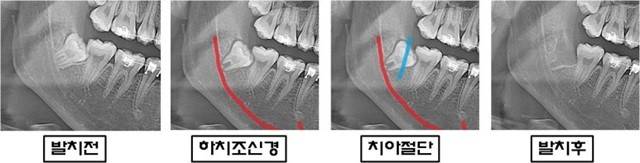

하치조신경을 피해서 사랑니 치아를 절단한 후 발치한 X-ray 사진 | 출처: 림플란트치과의원

사랑니 발치는 간단한 치료로 보일 수 있지만, 매복 사랑니나 신경과 밀접하게 위치한 사랑니의 경우 수술적 기술이 매우 중요합니다. 이때 구강악안면외과 전문의를 찾으면 턱뼈와 신경 구조에 대한 깊은 이해를 바탕으로, X-ray나 CT 스캔을 통해 신경의 위치와 사랑니의 관계를 정확히 파악한 후 발치를 진행합니다. 이를 통해 신경 손상의 위험을 최소화하고, 복잡한 사랑니 발치 수술을 보다 안전하게 수행할 수 있는 것입니다.

사랑니 발치 후 드물게 발생할 수 있는 부작용 중 하나는 하치조신경 마비입니다. 하치조신경은 턱뼈를 따라 지나가며, 이 신경은 아래쪽 입술, 턱, 잇몸의 감각을 담당합니다. 사랑니의 뿌리가 하치조신경과 가까운 경우, 발치 과정에서 이 신경이 손상될 수 있어 발치 후 입술, 턱, 혀의 감각이 둔해지거나 이상 감각이 발생할 수 있습니다.

특히 하치조신경과 가까이 있는 사랑니를 발치할 때는 세심한 주의가 필요합니다. 이로 인해 발치 후 감각 이상이 나타날 수 있는데요. 이러한 증상은 대개 일시적이지만, 경우에 따라 영구적으로 지속될 위험도 있습니다. 하치조신경 마비가 발생하면 입술이나 턱 부위의 감각이 무뎌지거나 찌릿한 느낌이 지속될 수 있으니 꼭 주의해야 합니다.